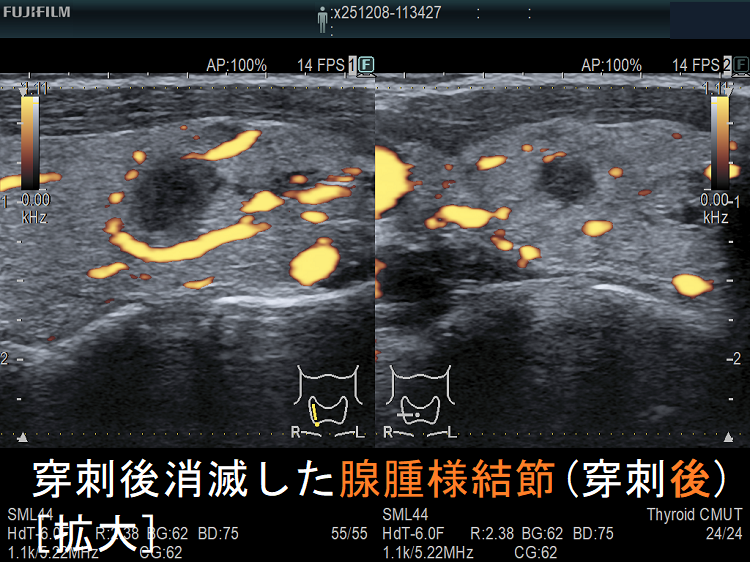

![穿刺後消滅した腺腫様結節(穿刺後) [拡大] 穿刺後消滅した腺腫様結節(穿刺後) [拡大]](../images/basic/basic5/images20251216212323.png)

![穿刺後消滅した腺腫様結節(穿刺後)ドプラーモード[拡大] 穿刺後消滅した腺腫様結節(穿刺後)ドプラーモード[拡大]](../images/basic/basic5/images20251216212330.png)